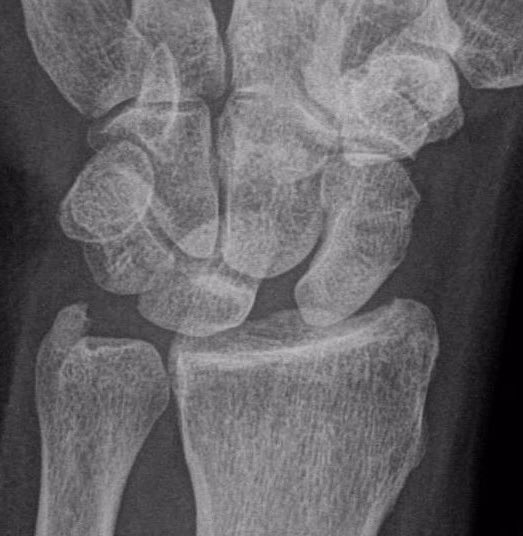

Clínicamente, el paciente refiere dolor en el dorso de la muñeca, especialmente al extenderla o al cargar peso. Puede observarse tumefacción, chasquidos o sensación de inestabilidad. A la exploración, es positiva la prueba de Watson (desplazamiento del escafoides con dolor y resalte). El diagnóstico se confirma mediante pruebas de imagen: la radiografía puede mostrar un aumento del espacio escafolunar (“signo de Terry Thomas”) (Figura 1), mientras que la resonancia magnética o la artro-RMN (Figura 2) pueden visualizar directamente la lesión del ligamento. En casos dudosos, la artroscopia de muñeca es el “gold standard” diagnóstico (Figura 3).